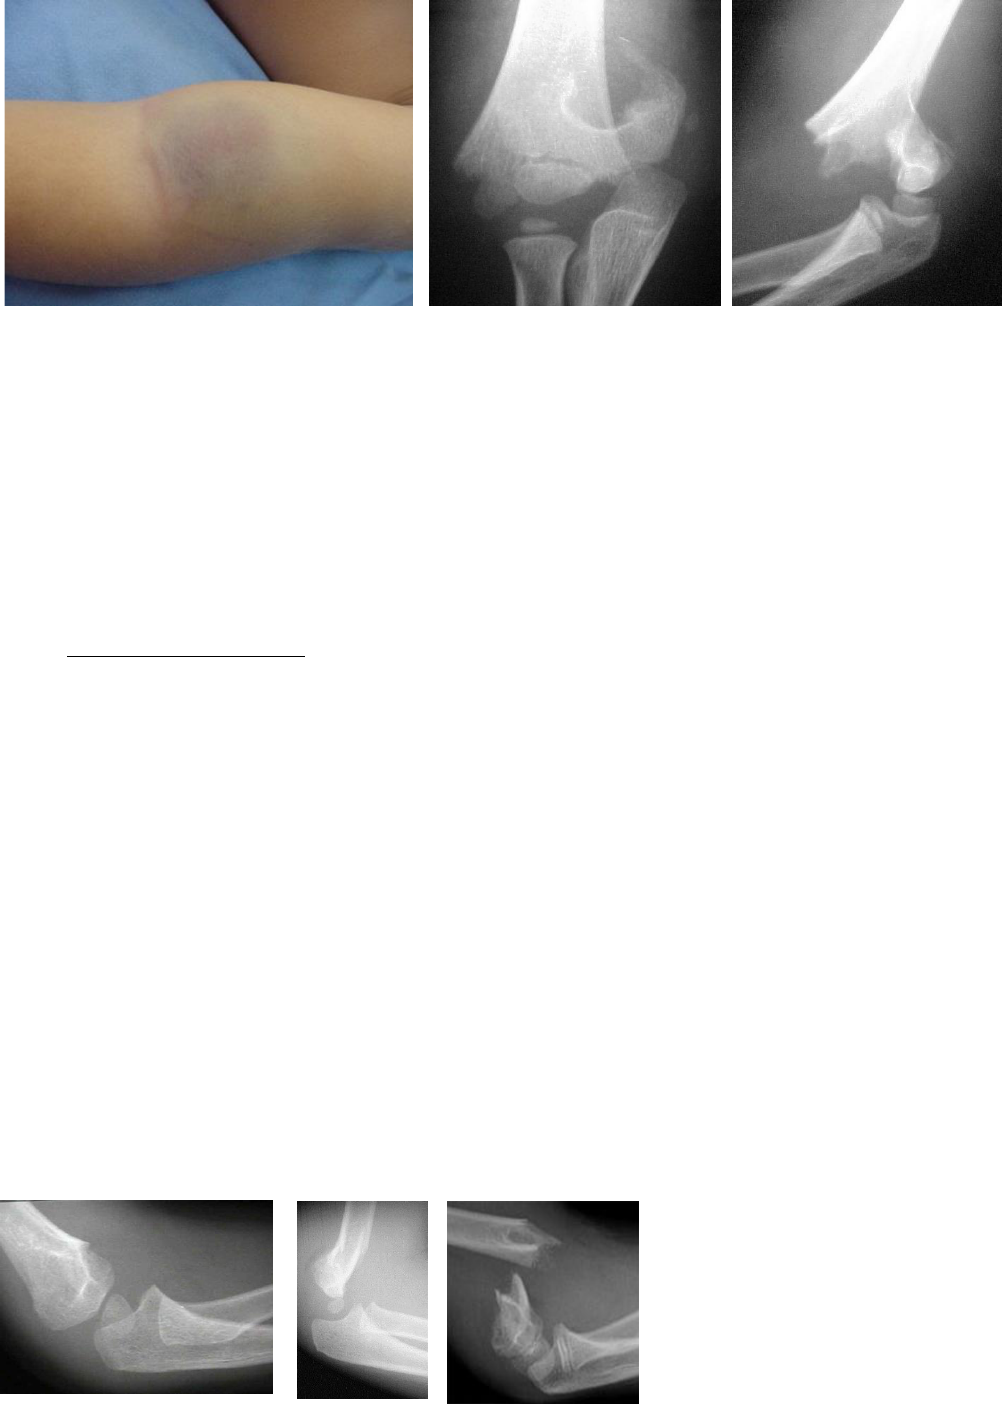

Caso: Menino, 6 anos de idade, sofreu queda de bicicleta com a mão esquerda espalmada no chão. A figura a seguir apresenta o aspecto clínico da criança. Você pode ver a fratura nas radiografias que foram realizadas prontamente.

A fx desse caso vem acompanhada de equimose e aumento de volume.

Qual região do úmero está fraturada? Distal.

O desvio mais comum nas fxs com mãos espalmadas é o posterior (98%) – queda com o membro superior em extensão.